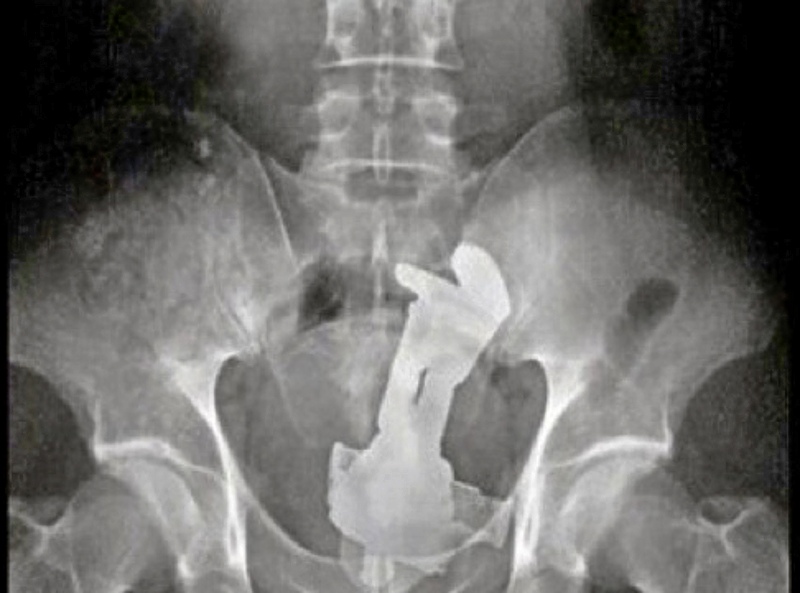

| Welk 'artefact' is te zien op dit plaatje (voor- en achternaam)? | Buzz Lightyear |